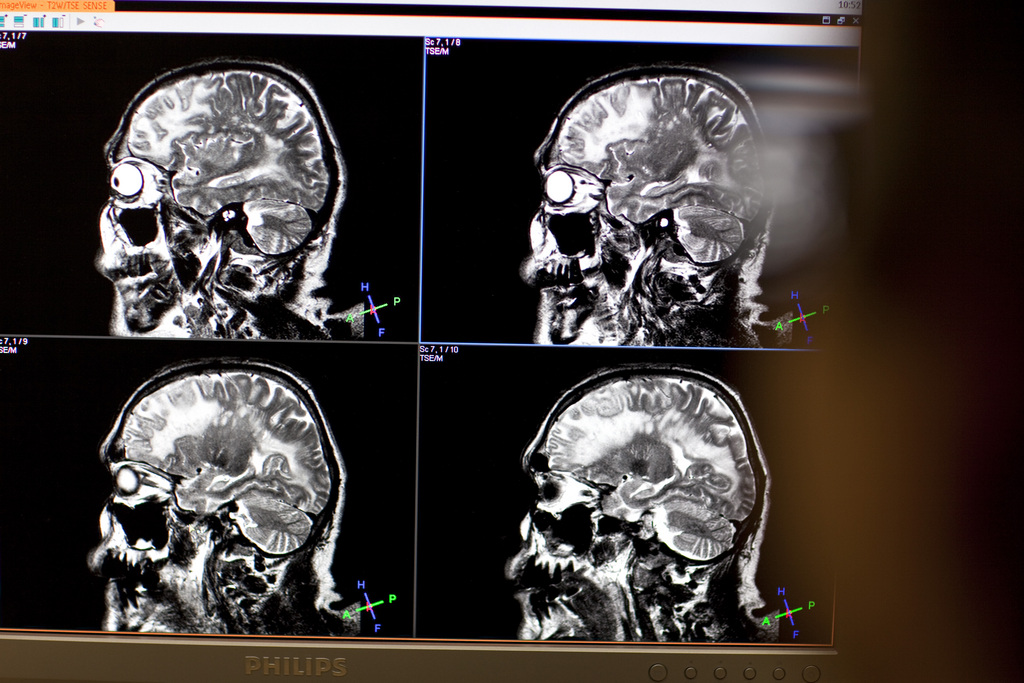

The study suggested that people who managed stress badly at a young age could experience repercussions on their cognitive abilities after the age of 50 Keystone

Young adults who are aggressive or cope badly with stress have a greater risk of suffering from memory problems decades later in middle age, a new study has revealed.